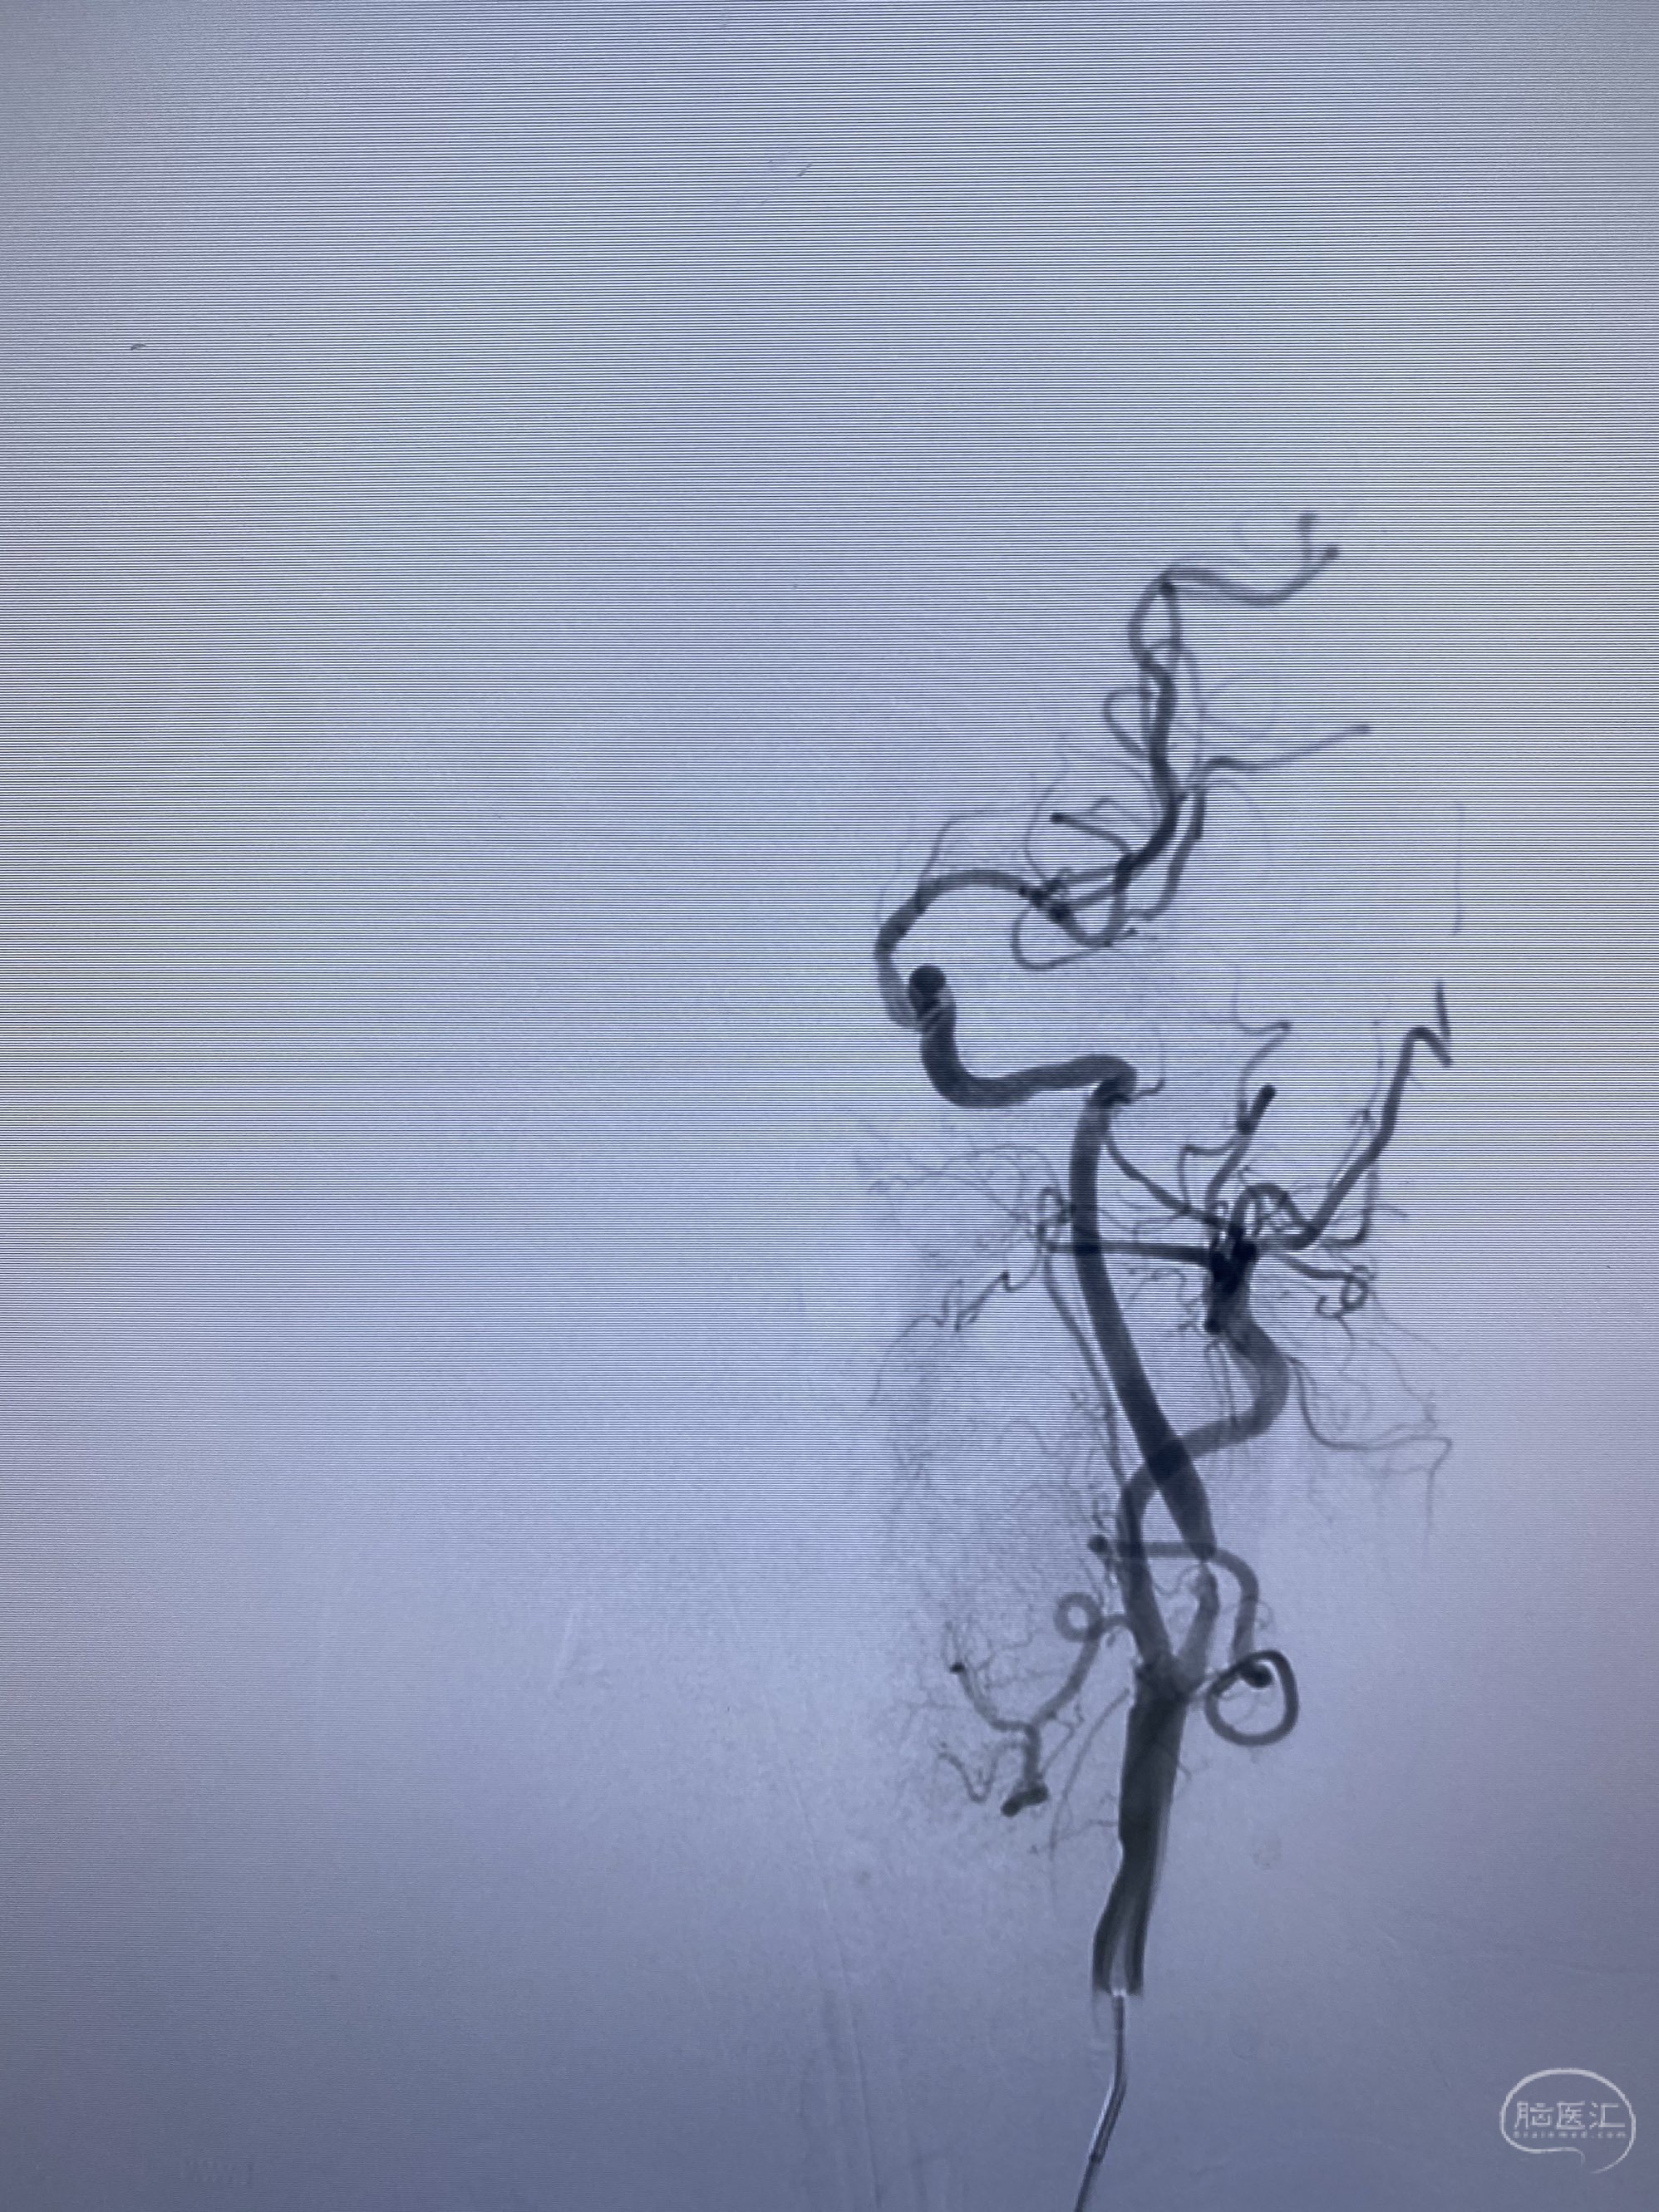

今日手术,TJG,M62Y,一期左侧颈动脉狭窄支架植入,二期椎动脉V4段多发夹层动脉瘤伴狭窄,常规支架辅助栓塞方法复杂又危险,血流导向装置植入快捷又安全。南阳市中心医院神经内科脑血管病介入团队pipeline flexFD植入两人导师资格。

椎动脉颅内段多发夹层动脉瘤伴载瘤动脉狭窄pipeline flex植入

今日手术,TJG,M62Y,一期左侧颈动脉狭窄支架植入,二期椎动脉V4段多发夹层动脉瘤伴狭窄,常规支架辅助栓塞方法复杂又危险,血流导向装置植入快捷又安全。南阳市中心医院神经内科脑血管病介入团队pipeline flexFD植入两人导师资格。